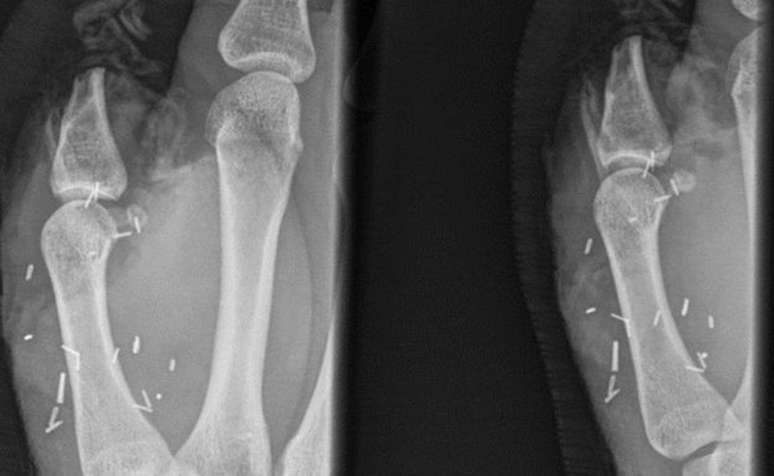

Cirurgiões tentaram reimplantar o polegar decepado duas vezes

Foto: South Eastern Sydney Local Health District / BBC News Brasil